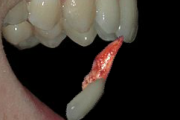

Krooni murrud